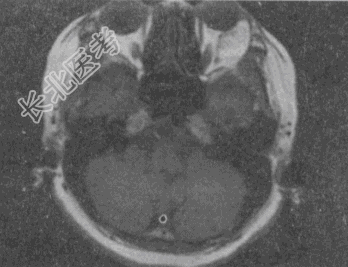

- 单项选择题女,52岁, 左眼球突出20余年,T

均正常, 影像检查如图所示,最可能的诊断是